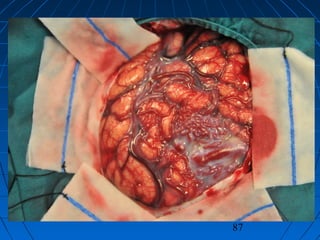

 S.Ç.: 32 yaşında kadın hastaS.Ç.: 32 yaşında kadın hasta

 Ani şiddetli başağrısı, B-KAni şiddetli başağrısı, B-K

CERRAHİCERRAHİ

 Sol frontoparyetal geniş kranyotomiSol frontoparyetal geniş kranyotomi

 AVM’nin total rezeksiyonuAVM’nin total rezeksiyonu